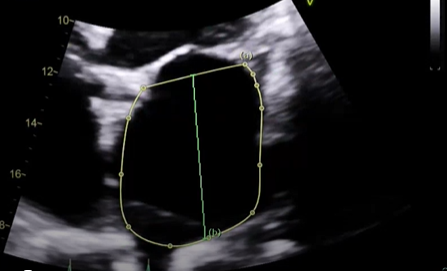

what measure measurement is this, explain how would want to measure this and what View,

Measured the LA area and length in A4C, at its largest dimension before the leaflet tips (MV) open at end-systole, want to exclude the Pulmonary vein and mitral annulus, this is when you need to trace the chamber and length. the normal LA area is going to be less than or equal to 20 or 24? (THIS IS NOT OUT LAV INDEX)